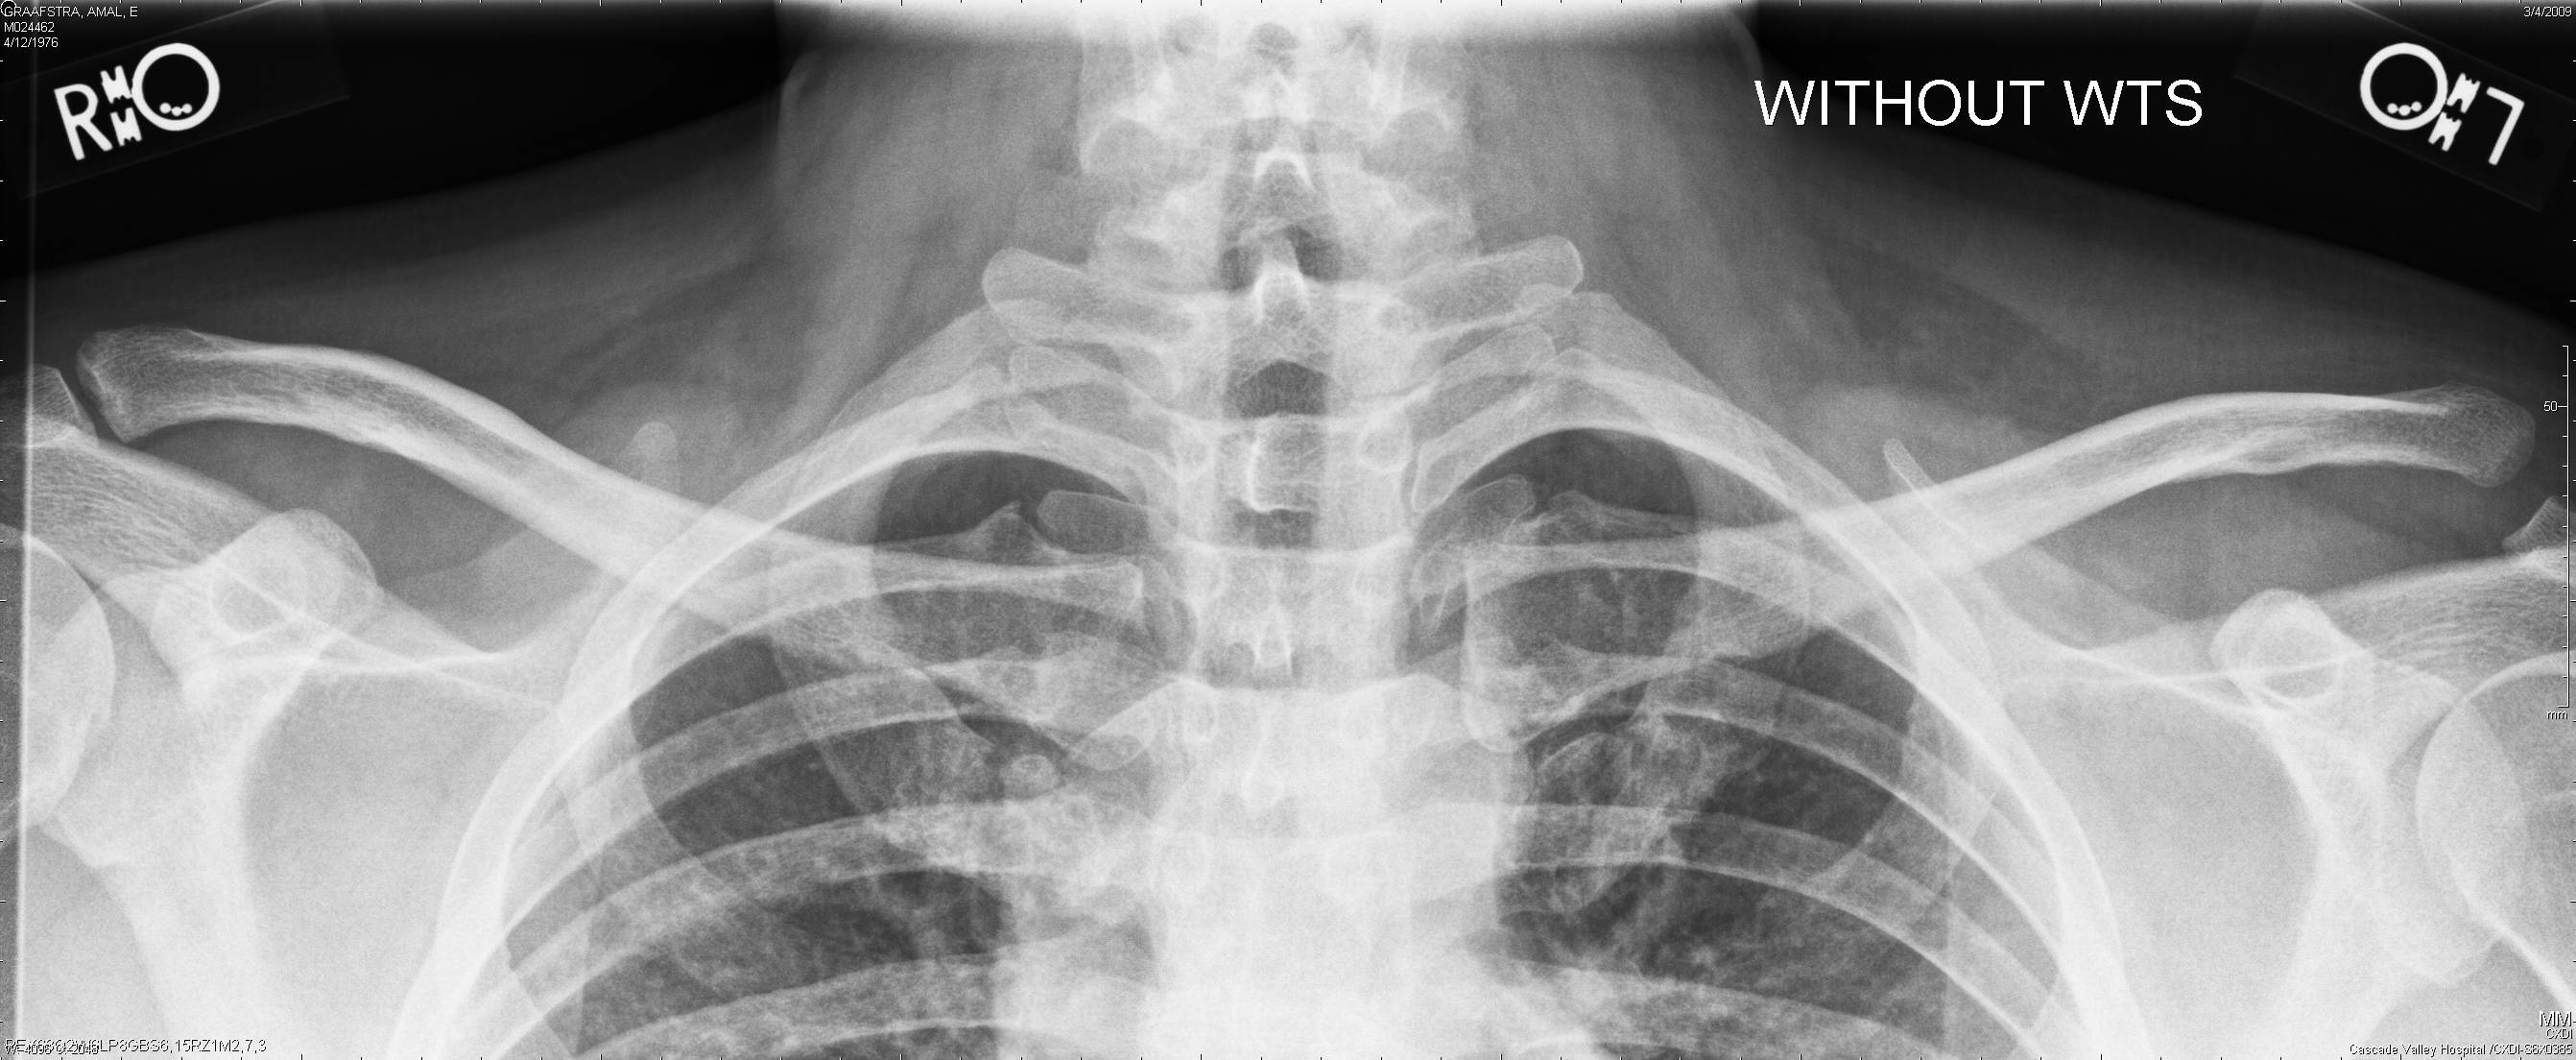

With Weight And Without Weightmarkers.

It is commonly caused by a fall directly on the point of the shoulder or a direct blow received in a contact sport. When it comes to diagnosing the subluxation of ac joint, radiology is performed as standard initial. Diagnosis is made with bilateral focused shoulder radiographs to assess for ac and cc interval widening.

Ac joint space is usually <5mm. The most common etiologies of pain are posttraumatic. Use a focused physical exam and imaging to make the diagnosis.